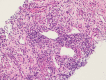

Figure 2

Figure 2. Renal biopsy revealed features of chronic inflammation of the kidney.

The interstitium shows moderate infiltration of mixed inflammatory cells comprised of lymphocytes, plasma cells, many histiocytes, eosinophils, and some neutrophils with focal area of necrosis.